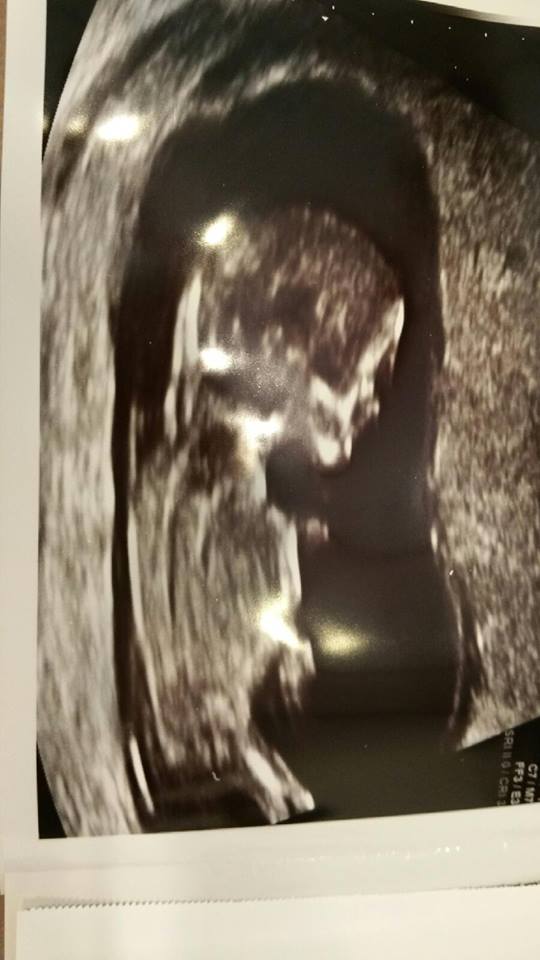

Anyone help predict gender. Baby measured at 12w4d for this scan. Tech said she was 80% sure it was a girl, but I am not sure, will find out 2/13, but am impatient and want to have others opinions before then.